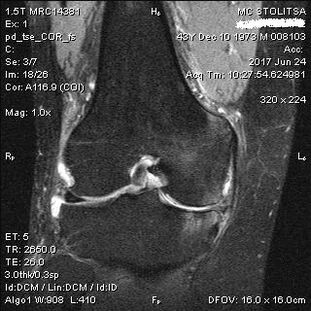

Dijagnoza artroze koljenskog zgloba odvija se u ordinaciji reumatologa ili ortopeda. Liječnik pregledava zahvaćeni zglob, palpira ga, sluša pritužbe i postavlja dodatna pitanja. Obavlja nekoliko testova - na primjer, traži od pacijenta da savije nogu ili napravi nekoliko koraka. Zatim, ako je potrebno razjasniti stadij bolesti ili prirodu patoloških promjena, uputit će vas na dodatne studije. Na primjer, za kompjutoriziranu tomografiju ili radiografiju.